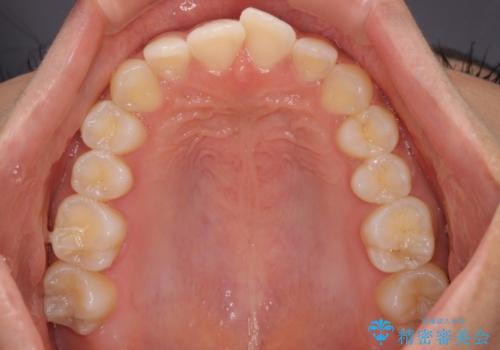

前歯のデコボコを治したい インビザライン・モデレートによる矯正治療

- 上下前歯の叢生を気にして来院された患者様です。

インビザラインでの治療を希望されていて、デコボコの程度が中等度であり、安価なパッケージにて対応可能と判断されたため、インビザライン・モデレートを用いて矯正治療を行うこととしました。

インビザライン・モデレートは、製作できるアライナーの枚数に制限があるため、移動可能な量に限りがあるものの、インビザライン・ライトよりも枚数が多いため、幅広い症例に対応可能です。